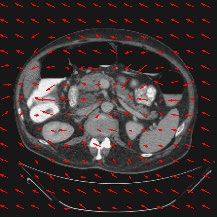

Transformers have made remarkable progress towards modeling long-range dependencies within the medical image analysis domain. However, current transformer-based models suffer from several disadvantages: (1) existing methods fail to capture the important features of the images due to the naive tokenization scheme; (2) the models suffer from information loss because they only consider single-scale feature representations; and (3) the segmentation label maps generated by the models are not accurate enough without considering rich semantic contexts and anatomical textures. In this work, we present CASTformer, a novel type of generative adversarial transformers, for 2D medical image segmentation. First, we take advantage of the pyramid structure to construct multi-scale representations and handle multi-scale variations. We then design a novel class-aware transformer module to better learn the discriminative regions of objects with semantic structures. Lastly, we utilize an adversarial training strategy that boosts segmentation accuracy and correspondingly allows a transformer-based discriminator to capture high-level semantically correlated contents and low-level anatomical features. Our experiments demonstrate that CASTformer dramatically outperforms previous state-of-the-art transformer-based approaches on three benchmarks, obtaining 2.54%-5.88% absolute improvements in Dice over previous models. Further qualitative experiments provide a more detailed picture of the model's inner workings, shed light on the challenges in improved transparency, and demonstrate that transfer learning can greatly improve performance and reduce the size of medical image datasets in training, making CASTformer a strong starting point for downstream medical image analysis tasks.